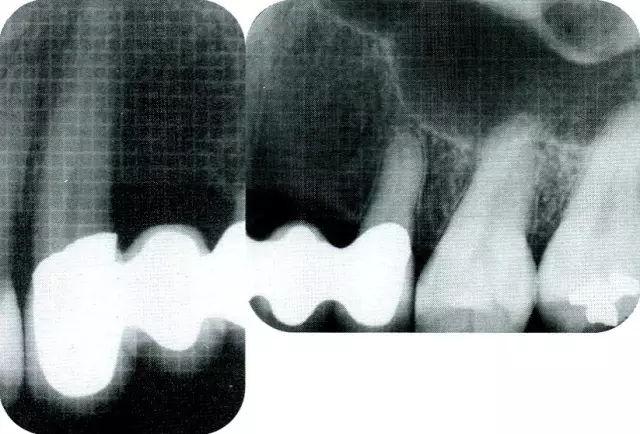

640.webp (3).jpg

▲圖7-4  術(shù)后1年2個月再翻開看的情況。與圖7-1的骨缺損狀態(tài)相比可知形成了臨床性骨再生。

640.webp (4).jpg

▲圖7-5  此狀態(tài)下,左下5的遠(yuǎn)中存在牙槽骨不平整,因此進(jìn)行了骨修整。同時,將骨膜留存,進(jìn)行了齦瓣根尖側(cè)移動術(shù),去除了牙周袋。